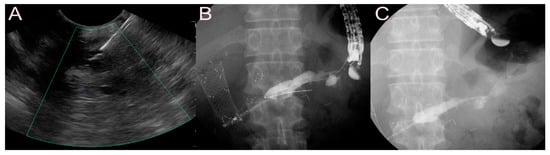

2.5. Stent for EUS-Guided Creation of Entero-Enteric Anastomosis